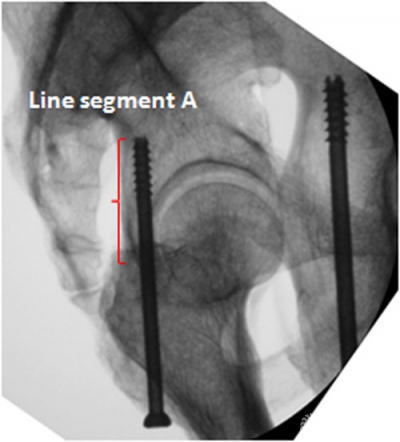

The angles α, β and γ measured onthe CT images at the level of the middle height of the acetabulum of specimens are summarised in table 1. The mean values of angles α, β and γ for specimens were 29.3 (range, 26.5-34.2), 8.1 (range, 6.9-9.8) and 93.7 (range, 85.7-103.6) degrees, respectively. Whilecollecting the obturator oblique radiographs of the acetabulum, the directionof the radiological beam was at an angle of 45 degrees with the line intersecting the axial plane and the coronalplane. Line A was at an angle of approximately 30 degrees with the lineintersecting the axial plane and the coronal plane. Accordingly, Line A was atan angle of approximately 15 degrees with the direction of the radiologicalbeam when collecting the obturator oblique view. That is to say, the tangentialprojection of the PCPC can be obtained by rotating the C-arm fluoroscopic beam 15degrees outward from the position where the obturator oblique view is collected.On this view, the projection of the PCPC appears as a nearly straight linesegment (Line segment A) between the lesser and greater sciatic notches (Figure 4). Line C was nearlyperpendicular to line A, which means that the entire outline of the acetabulumcan be almost demonstrated on the tangential views of the PCPC. In a similarway, the tangential view of the medial wall of the acetabulum can be obtainedby rotating the radiological beam angle β outward from the position where theanteroposterior view of pelvis is taken. On this view, the medial wall alsoappears as a distinct straight line (Figure5).

Figure4 On the tangential view of the posterior cortex of the posteriorcolumn, the posterior cortex appears as a nearly straight line segment betweenthe lesser and greater sciatic notches (Line segment A, the red curly brace).